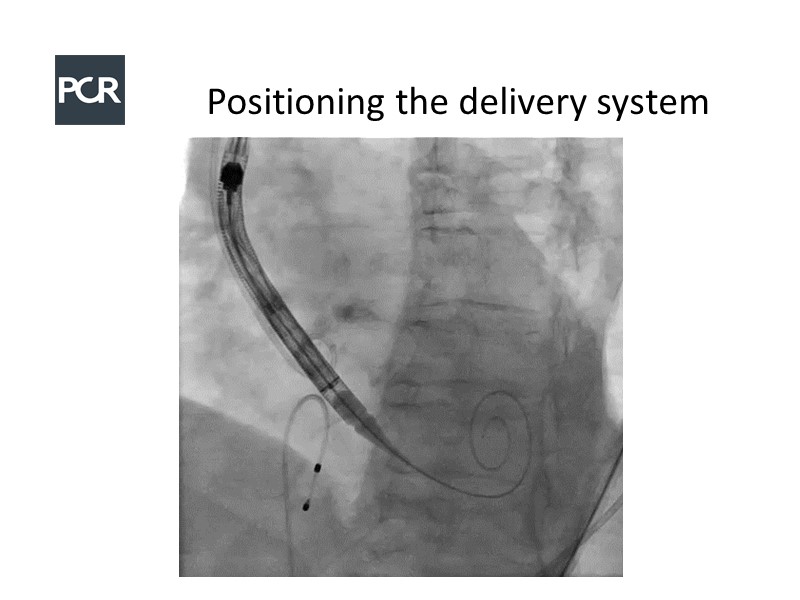

In this session, a panel of experts introduce the VitaFlow TAVI system, a good option for patients with complex anatomies. They also present the five-year results of VitaFlow in severe aortic stenosis.